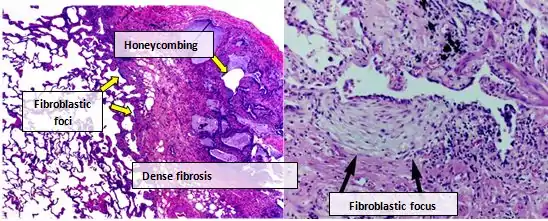

According to the updated 2011 guidelines, in the absence of a typical UIP pattern on HRCT, a surgical lung biopsy is required for confident diagnosis.[3]

Histologic specimens for the diagnosis of IPF must be taken at least in three different places and be large enough that the pathologist can comment on the underlying lung architecture. Small biopsies, such as those obtained via transbronchial lung biopsy (performed during bronchoscopy) are usually not sufficient for this purpose. Hence, larger biopsies obtained surgically via a thoracotomy or thoracoscopy are usually necessary.[3][9]

Lung tissue from people with IPF usually show a characteristic histopathologic UIP pattern and is therefore the pathologic counterpart of IPF.[3] Although a pathologic diagnosis of UIP often corresponds to a clinical diagnosis of IPF, a UIP histologic pattern can be seen in other diseases as well, and fibrosis of known origin (rheumatic diseases for example).[1][3] There are four key features of UIP including interstitial fibrosis in a 'patchwork pattern', interstitial scarring, honeycomb changes and fibroblast foci.

Fibroblastic foci are dense collections of myofibroblasts and scar tissue and, together with honeycombing, are the main pathological findings that allow a diagnosis of UIP.